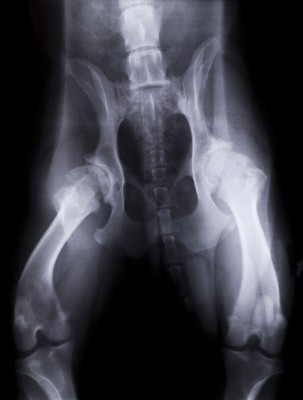

Hip Dysplasia

Canine hip dysplasia is a degenerative, painful condition where the hip joints have developed abnormally. The head of the thigh bone (femur) does not fit properly into the hip socket (acetabulum). These “ball and socket” joints become malformed and unstable, causing inflammation and weakness.